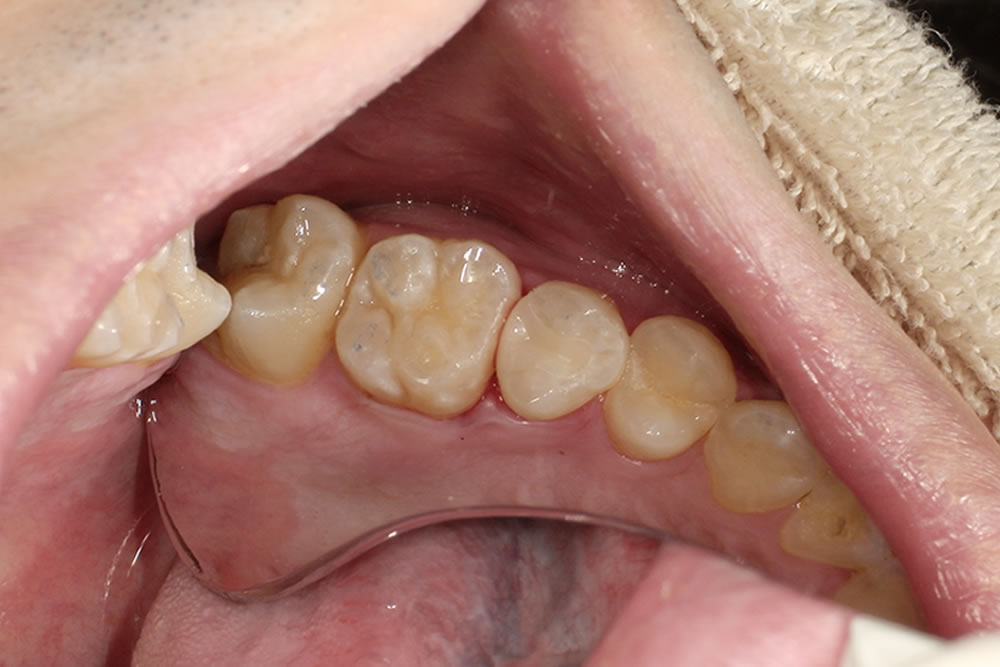

こちらの患者さまは以前から当院に通院されている方で、定期的な通院の中で今回の虫歯が見つかりました。

来院時のお口の状態

診査とレントゲン検査の結果、左上の奥歯(左上5番)の歯と歯の間に虫歯が認められました。歯と歯の間の虫歯は見た目では分かりにくいことが多く、レントゲン検査で発見されることも少なくありません。

セラミックインレー・CRによる修復

今回は経過観察中に特に症状が現れなかったため、患者さまと相談のうえセラミックインレー(セラミックのつめ物)で治療を行いました。

セラミックは透明感があり、天然歯に近い自然な見た目に仕上げることができます。また表面がなめらかで汚れが付きにくく、二次虫歯(詰め物の周囲に再びできる虫歯)のリスクを抑えるという特徴があります。

なお、隣の歯には浅く小さな虫歯が確認されたため、その部分のみを削り、CR(コンポジットレジン)という白い樹脂材料で修復を行いました。

治療後の患者さまの感想・今後の予定

治療後は「自然な見た目になってとても満足しています」と喜んでいただけました。今後も定期的なメンテナンスでお口の状態を確認しながら、虫歯の再発を予防していく予定です。

| 年齢/性別 | 20代男性 |

| 治療期間・回数 | 2ヵ月(通院3回) |

| 治療部位 | 左上5番 |

| 治療費 | セラミックインレー53,900円(税込)※印象代含む |

| リスクなど | ・削る治療のため治療後にしみることがあります。 ・強い衝撃により詰め物が破折する可能性があります。 |